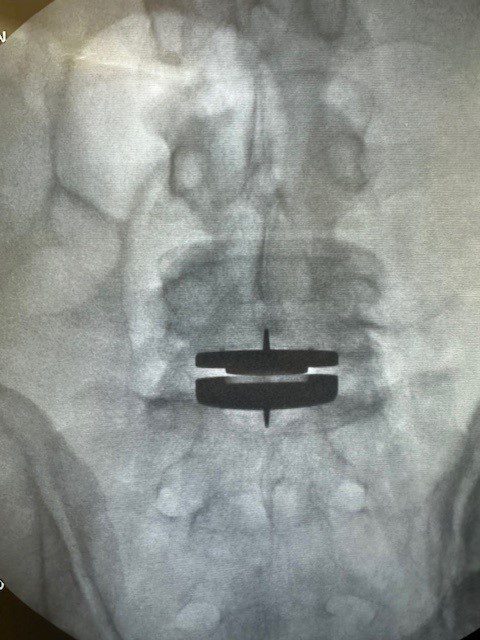

Mike Hewitt, a 55-year-old retired Air Force veteran, didn’t think he would ever again be able to enjoy running, golfing, or playing with his grandchildren. For over two decades, he lived with chronic back pain from a previous injury. Despite years of physical therapy and treatments, his pain persisted. Thanks to a recent prodisc L TDR surgery, he is regaining his quality of life.

“With the continual improvement in insurance coverage, more of my patients will be able to benefit from disc replacement technology... Using a minimally invasive anterior approach, my patients also benefit from a much faster recovery and return to active life, while decreasing the likelihood of adjacent level degeneration.”